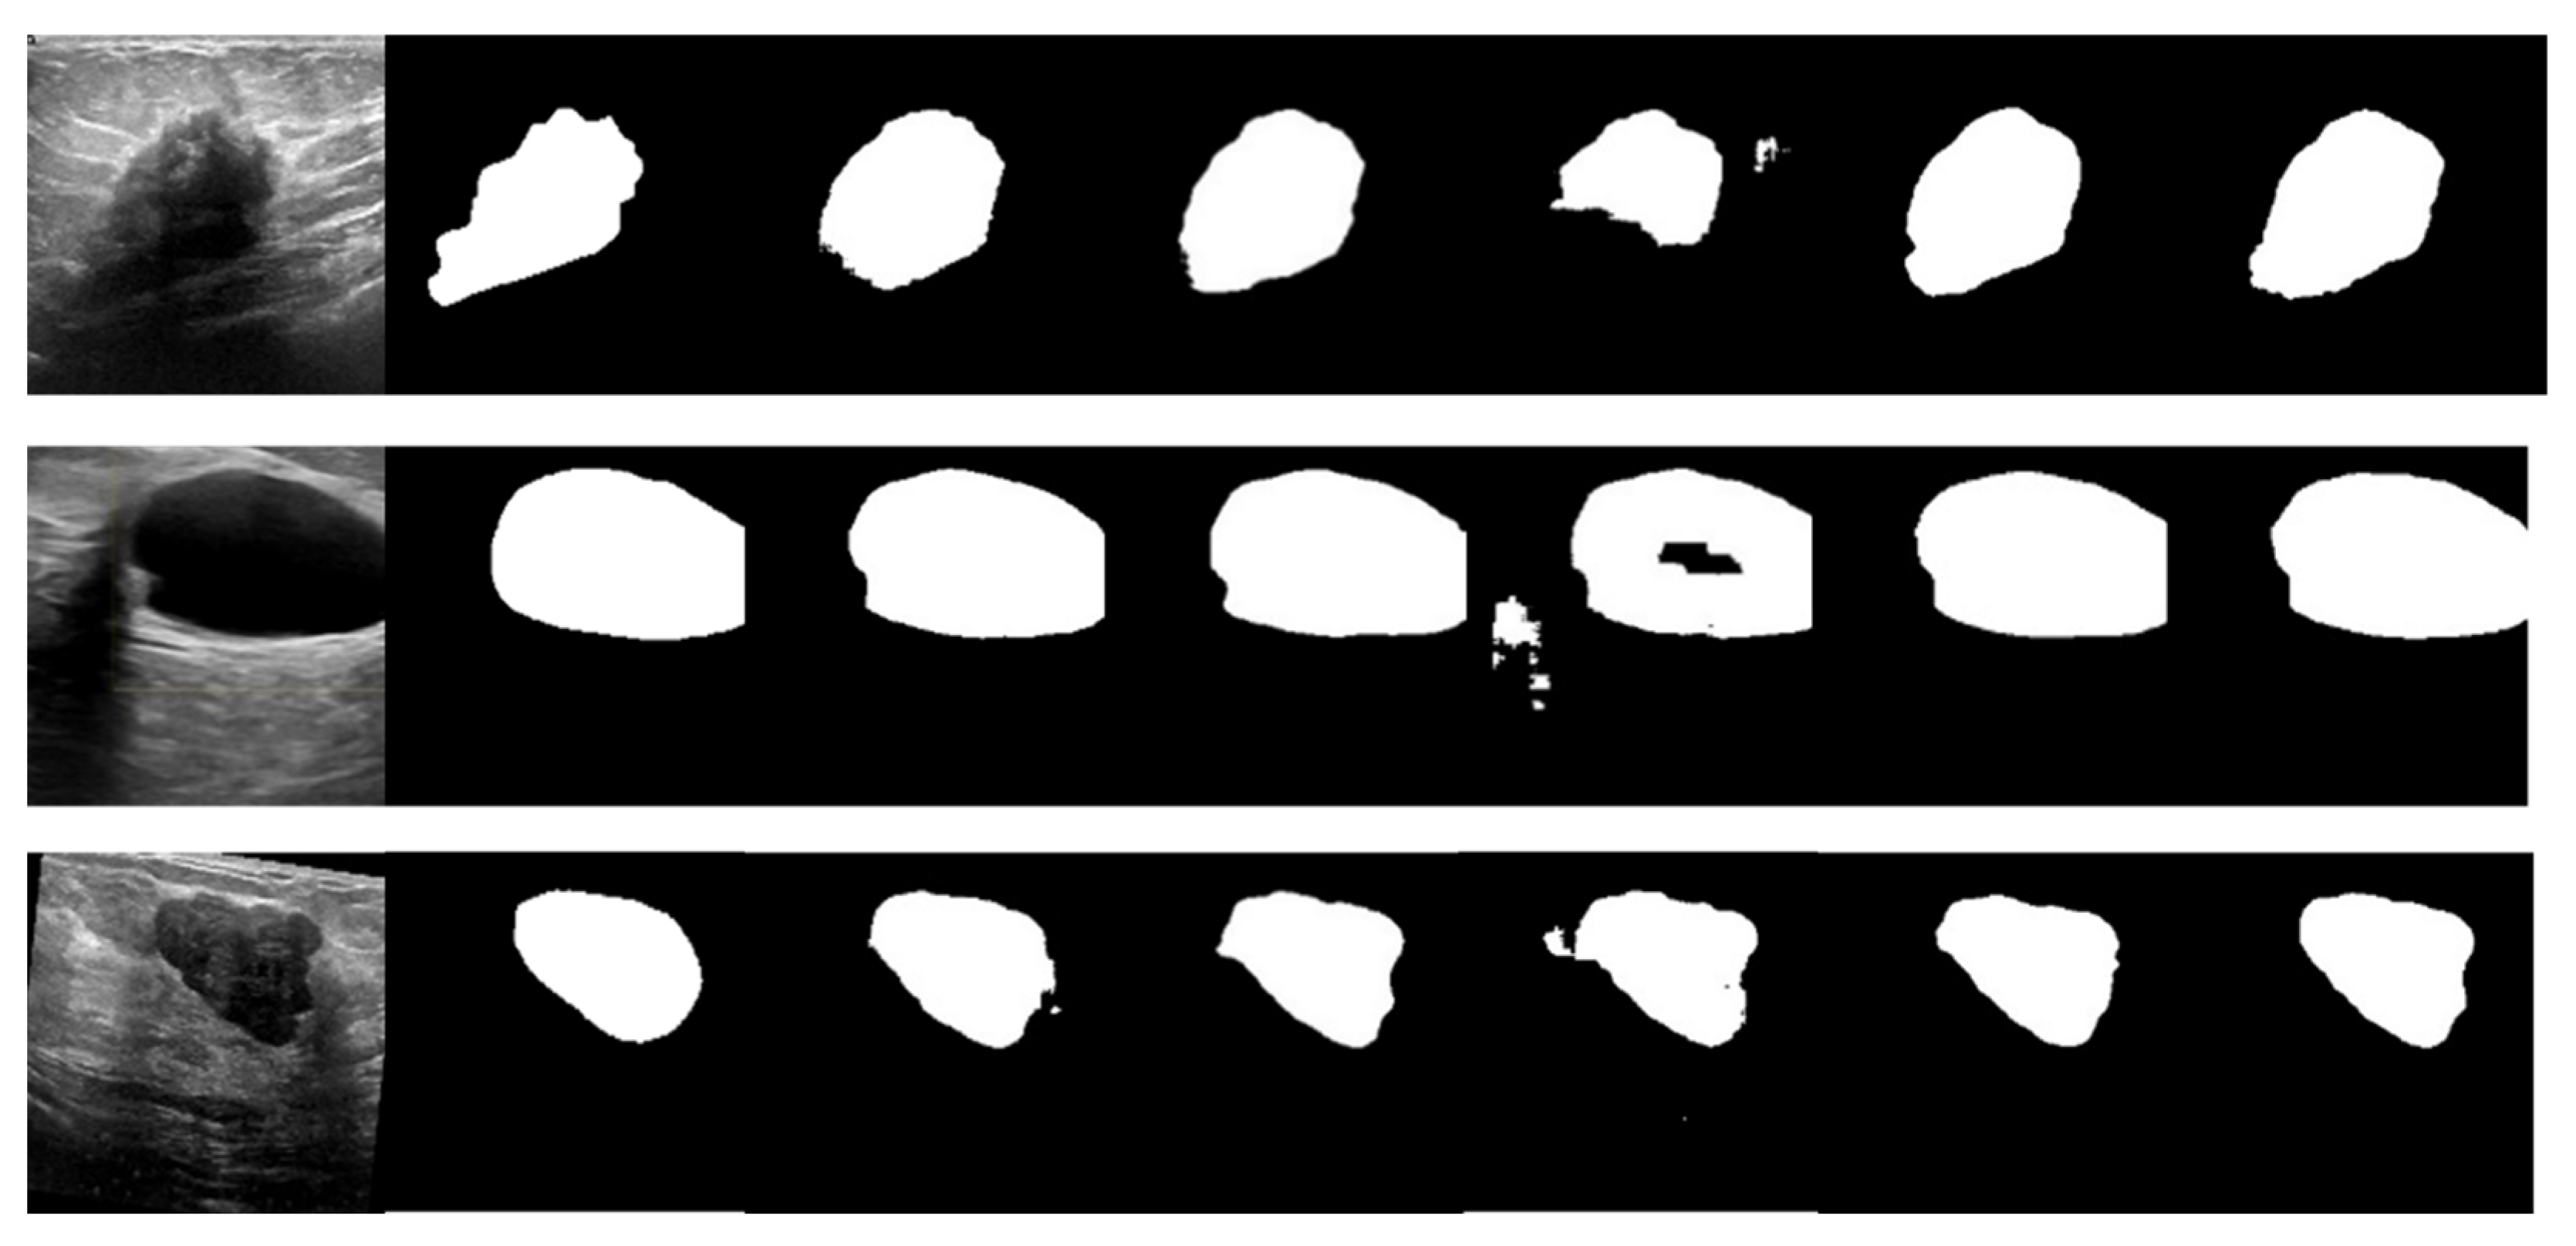

- Finally, we test and demonstrate the performance of LcmUNet on three medical image segmentation datasets: ISIC2018, BUSI, and Kvasir-SEG. Specifically, with only 1.49M parameters, we obtained segmentation accuracies of 85.19%, 63.99%, and 81.89% on the three datasets using a NVIDIA 3060 GPU, further highlighting the superiority of LcmUNet in the field of medical image segmentation.

4.2. Comparative Experiments

| Network | ISIC2018 | Kvasir-SEG | BUSI | |||||||||

| Iou | F1 | Re | Pr | Iou | F1 | Re | Pr | Iou | F1 | Re | Pr | |

| UNet | 80.17 | 88.71 | 86.61 | 91.50 | 76.20 | 86.13 | 85.82 | 87.55 | 52.12 | 67.80 | 65.21 | 76.36 |

| DeepLabv3+ | 82.07 | 89.70 | 89.01 | 91.61 | 79.15 | 88.04 | 88.40 | 88.57 | 58.72 | 73.16 | 72.00 | 78.44 |

| Fcn8s | 78.26 | 87.14 | 85.58 | 90.25 | 59.96 | 74.50 | 75.29 | 76.54 | 53.31 | 68.45 | 66.00 | 75.40 |

| SegNet | 79.93 | 87.55 | 90.56 | 88.34 | 79.33 | 88.20 | 86.55 | 90.62 | 58.85 | 73.37 | 72.21 | 75.99 |

| AttUNet | 80.92 | 89.20 | 88.48 | 90.45 | 78.48 | 88.55 | 87.01 | 89.13 | 56.30 | 71.34 | 67.84 | 77.14 |

| UNext | 82.00 | 89.87 | 88.98 | 91.29 | 77.57 | 86.99 | 87.67 | 88.05 | 60.74 | 75.35 | 77.05 | 75.46 |

| ResUnet | 77.86 | 87.27 | 86.30 | 88.34 | 67.10 | 79.93 | 78.55 | 83.02 | 44.23 | 60.79 | 57.15 | 73.25 |

| LcmUNet (Ours) | 85.19 | 91.81 | 92.07 | 92.99 | 81.89 | 89.92 | 88.93 | 91.79 | 63.99 | 77.37 | 79.96 | 76.69 |